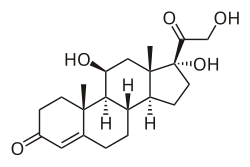

Saliva testing also has specific uses in clinical and experimental psychological settings. Due to its ability to provide insight into human behavior, emotions, and development, it has been used to investigate psychological phenomenon such as anxiety, depression, PTSD, and other behavioral disorders.[11] Its primary purpose is to test cortisol and alpha amylase levels, which are indicative of stress levels. Salivary cortisol is a good stress index, with increased levels of cortisol correlating positively with increased levels of stress. Cortisol levels rise slowly over time and take a while to return to base level, indicating that cortisol is more associated with chronic stress levels.[12] Alpha amylase, on the other hand, spikes quickly when confronted with a stressor and returns to baseline soon after the stress has passed, making salivary amylase measurement a powerful tool for psychological research studying acute stress responses.[12] Samples are usually collected from participants by having them drool through a straw into a collection tube while experiencing a stimulus, with samples taken every few minutes to record the gradual change in stress hormone levels. Because the collection of saliva samples is non-invasive, it has the advantage of not introducing further stress on the participant that may otherwise distort results.[13]

In more specific studies looking at the link between cortisol levels and psychological phenomena, it has been found that chronic stressors such as life-threatening situations (example: diseases), depression, and social or economic hardship correlate with significantly higher cortisol levels.[13] In situations where a subject undergoes induced anxiety, high cortisol levels correspond with experiencing more physiological symptoms of nervousness, such as increased heart rate, sweating, and skin conductance.[14] Additionally, a negative correlation was discovered between baseline levels of cortisol and aggression.[15] Salivary cortisol levels can thus provide insight into a number of other psychological processes.

Cortisol and melatonin aberrations

In 2008 the Endocrine Society published diagnostic guidelines for Cushing's syndrome, wherein they recommended midnight salivary cortisol testing on two consecutive days as one possible initial screening tool.[21] A 2009 review concluded that late-night salivary cortisol testing is a suitable alternative to serum cortisol testing for diagnosing Cushing's syndrome, reporting that both sensitivity and specificity exceeded ninety percent.[22] In 2010 Sakihara, et al., evaluated the usefulness and accuracy of salivary, plasma, and urinary cortisol levels and determined salivary cortisol to be the "method of choice" for Cushing's syndrome screening.[23] In 2008 Restituto, et al., found early morning salivary cortisol to be "as good as serum" as an Addison's disease screening technique.[24] In 2010 Bagcim et al., determined that saliva melatonin levels "reflect those in serum at any time of the day" and are a reliable alternative to serum melatonin to study the pineal physiology in newborns.[25] A 2008 review article described saliva melatonin testing as a "practical and reliable method for field, clinical, and research trials".[26]